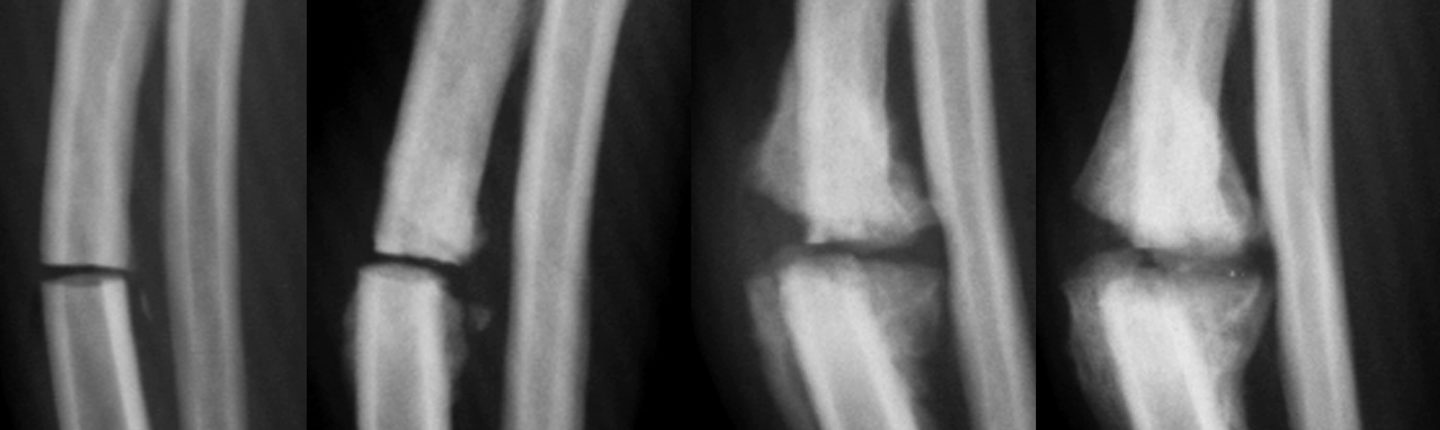

retained cartilaginous core signalment

6-12 mo age

large giant breeds, saint bernards

OC of distal ulnar metaphysis/physis

often bilateral and incidental

retained cartilaginous core

2 parallel lines with Lucent in the middle going towards the ulna